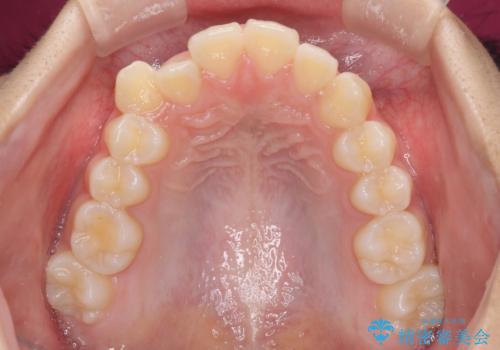

- 前歯のデコボコと八重歯を気にして来院された患者様です。

本人はあまり実感はありませんでしたが、同席されたご家族より口がすぐに開いてしまうことを指摘されていました。

口元に力の入る歯列であったため、上顎左右第一小臼歯4本を抜歯するワイヤー矯正を行うこととしました。